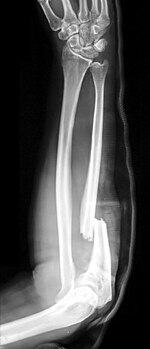

Galeazzi fracture Ricardo Galeazzi radius shaft fracture with dislocation of distal radioulnar joint blow to forearm Galeazzi fracture Archived 2017-12-01 at the Wayback Machine at eMedicine Galeazzifraktur 1 THWZ.jpg

Monteggia fracture Giovanni Battista Monteggia proximal ulna fracture with dislocation of radial head blow to forearm Monteggia fracture at Who Named It? Monteggia Fracture.jpg